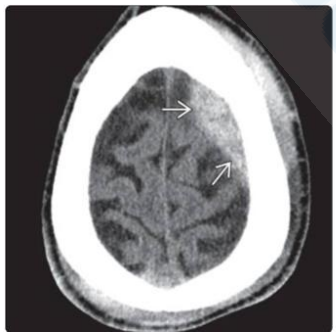

Com base na Figura 1 abaixo, assinale a alternativa que indica a lesão apresentada na tomografia.

Figura 1